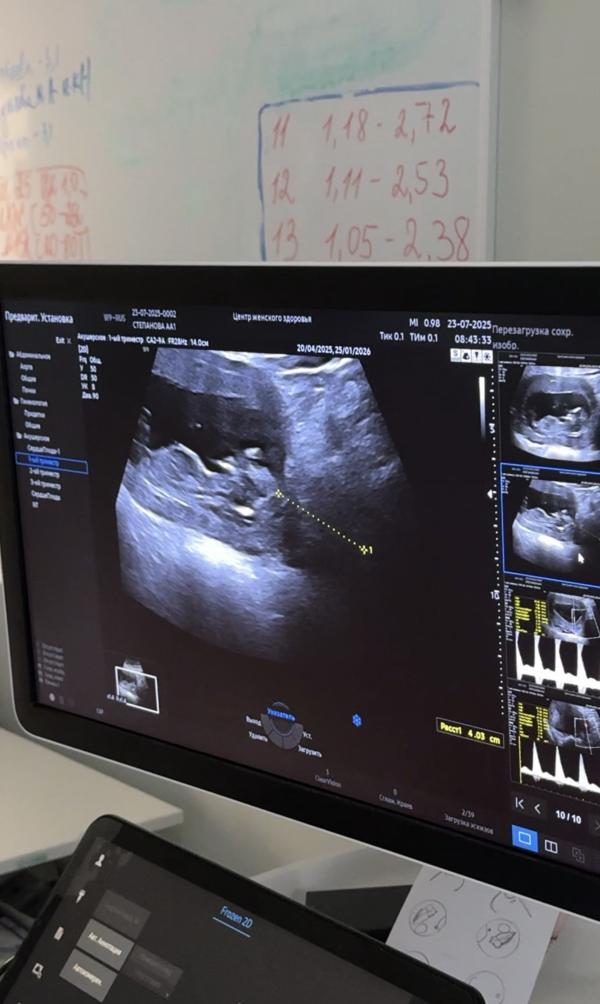

Вчера был первый скрининг ,фотографии разрешили сделать с монитора ,я вот не пойму это половой бугорок или нет? И судя по нему мальчик ?пол не стали предполагать ,сказали что у них до 14 недели всё одинаково

Тут не видно половой бугорок, вообще непонятно что дали сфоткать, не могли нормально приставить датчик чтоб профиль четко вырисовывался🥲

Ничего не понятно по фото. Но вообще не одинаково уже. Просто должен быть опытный специалист и хороший аппарат УЗИ. С дочкой мне 12-13 недель сказали и даже показали что к чему. Девочку определили по наличию двух полосочек на месте половых органов которые потом становятся половыми губами.